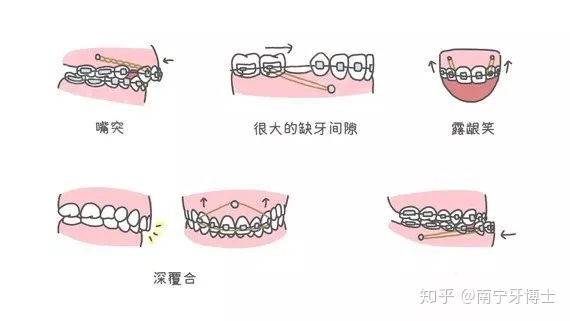

①缺牙引起的间隙过大

生活中,有不少患者的嘴型很好,脸型也不差,但是就是有很大的缺牙间隙,需要后牙向前移动来关闭间隙时。

②需要压低前牙

- 露龈笑:此类患者需要利用骨钉来压低上前牙,进而来缩短牙龈的高度;

- 深覆合:需要打骨钉来压低上前牙,有效地减小深覆合的程度、以防止咬合加深;

- 反颌:此时打骨钉,可以有效地压低下前牙,进而改善地包天的状况。

③个别牙齿倾倒可以利用骨钉快速“扶正”牙齿,让牙齿站起来。④个别牙齿不在队列中比如有埋伏牙,可以开窗后利用骨钉牵引让牙齿“归队”。⑤龅牙出现龅牙时,需要内收前牙。骨钉可以把突出去的前牙收回来。